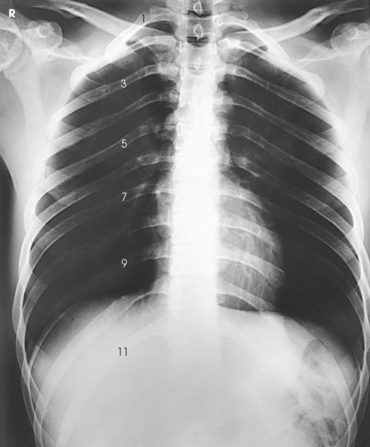

The 12 pairs of ribs are numbered consecutively from superiorly to inferiorly (Fig. 9-4; see Figs. 9-1 and 9-2). The rib number corresponds to the thoracic vertebra to which it attaches. Each rib is a long, narrow, curved bone with an anteriorly attached piece of hyaline cartilage, the costal cartilage. The costal cartilages of the first through seventh ribs attach directly to the sternum. The costal cartilages of the 8th through 10th ribs attach to the costal cartilage of the 7th rib. The ribs are situated in an oblique plane slanting anteriorly and inferiorly so that their anterior ends lie 3 to 5 inches (7.6 to 12.5 cm) below the level of their vertebral ends. The degree of obliquity gradually increases from the 1st to the 9th rib and then decreases to the 12th rib. The first seven ribs are called true ribs because they attach directly to the sternum. Ribs 8 to 12 are called false ribs because they do not attach directly to the sternum. The last two ribs (11th and 12th ribs) are often called floating ribs because they are attached only to the vertebrae. The spaces between the ribs are referred to as the intercostal spaces.

The position of the diaphragm varies with body habitus: It is at a higher level in hypersthenic patients and at a lower level in asthenic patients (Fig. 9-9). In sthenic patients of average size and shape, the right side of the diaphragm arches posteriorly from the level of about the 6th or 7th costal cartilage to the level of the 9th or 10th thoracic vertebra when the body is in the upright position. The left side of the diaphragm lies at a slightly lower level. Because of the oblique location of the ribs and the diaphragm, several pairs of ribs appear on radiographs to lie partly above and partly below the diaphragm.

Fig. 9-9 Diaphragm position and body habitus. A, A hypersthenic patient has a diaphragm positioned higher. B, An asthenic patient has a diaphragm positioned lower. C, Chest radiograph of a hypersthenic patient. D, Chest radiograph of an asthenic patient. Note position of diaphragm on these extremely different body types.